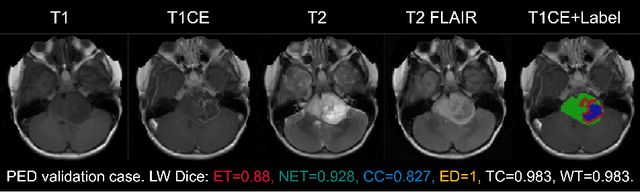

Abstract:Segmenting brain tumors in multi-parametric magnetic resonance imaging enables performing quantitative analysis in support of clinical trials and personalized patient care. This analysis provides the potential to impact clinical decision-making processes, including diagnosis and prognosis. In 2023, the well-established Brain Tumor Segmentation (BraTS) challenge presented a substantial expansion with eight tasks and 4,500 brain tumor cases. In this paper, we present a deep learning-based ensemble strategy that is evaluated for newly included tumor cases in three tasks: pediatric brain tumors (PED), intracranial meningioma (MEN), and brain metastases (MET). In particular, we ensemble outputs from state-of-the-art nnU-Net and Swin UNETR models on a region-wise basis. Furthermore, we implemented a targeted post-processing strategy based on a cross-validated threshold search to improve the segmentation results for tumor sub-regions. The evaluation of our proposed method on unseen test cases for the three tasks resulted in lesion-wise Dice scores for PED: 0.653, 0.809, 0.826; MEN: 0.876, 0.867, 0.849; and MET: 0.555, 0.6, 0.58; for the enhancing tumor, tumor core, and whole tumor, respectively. Our method was ranked first for PED, third for MEN, and fourth for MET, respectively.